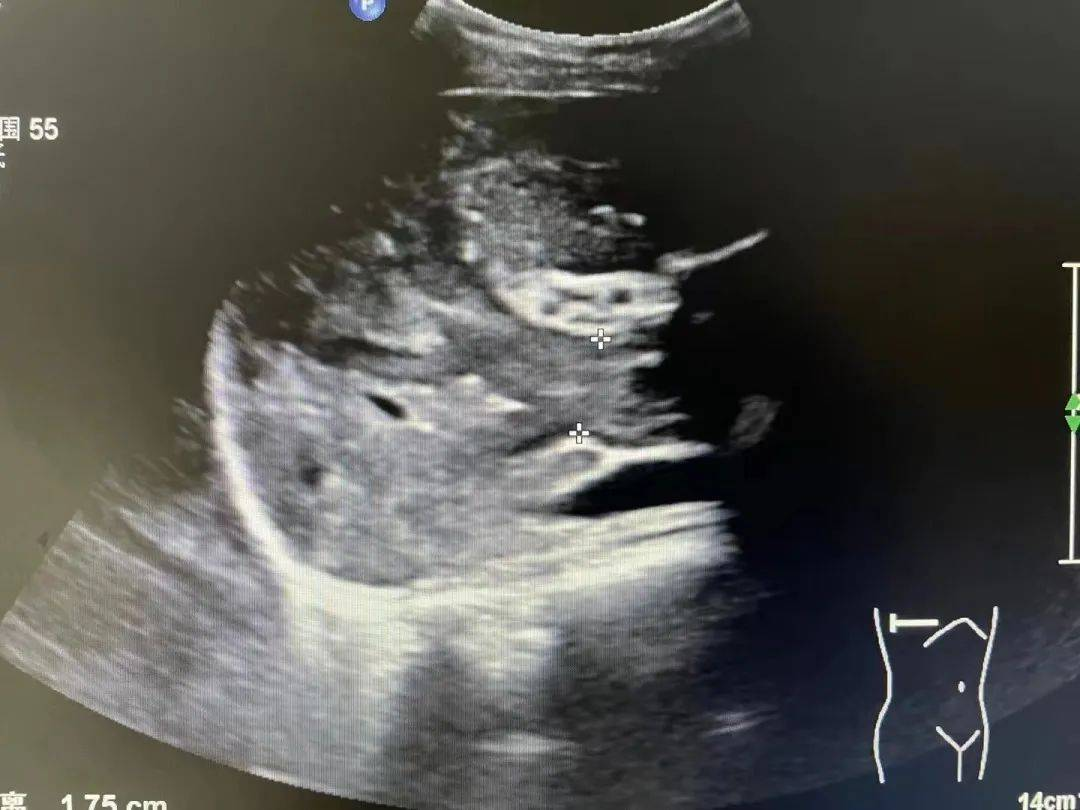

▲小丽的超声图

超声提示肝内肿瘤伴门静脉广泛癌栓,最终确诊为“肝癌晚期”。